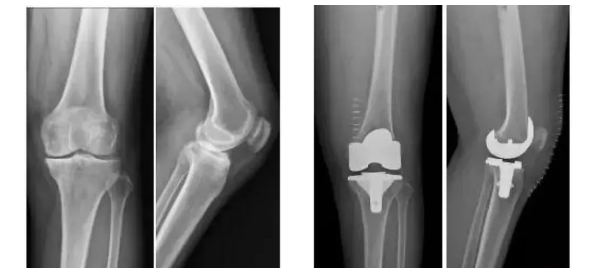

3D打印生物型人工膝關節在國內成功植入!

「全球shou款3D打印分區骨小梁生物型膝關節假體」

膝關節骨關節炎是一種退行性疾病,近年隨著經濟發展和人口老齡化趨勢日趨明顯,尤其是在中老年群體發病率較高,因此膝關節置換術需求量日益增長。此外,隨著居民生活水平的提高,大多患者對于膝關節置換術術后的生活質量和植入假體有了更高的要求,隨之假體在設計和創新方面也更精準、更便捷化。全球shou款3D打印分區骨小梁生物型膝關節假體正是在這種高需求與高期待的新形勢下應運而生。

本次植入的生物型膝關節假體在術中無需使用骨水泥,通過機械方式進行固定,即假體與骨組織的緊密結合,獲得假體的初始穩定性,遠期骨組織長入假體表面的微孔內部,實現由機械固定向生物.內鎖固定的轉化,zui終經過骨整合作用獲得良好固定,預期能夠獲得更長的假體壽命。此外,生物型膝關節假體避兔了骨水泥相關并發癥的發生,縮短了手術時間,zui大程度保留了骨組織。因而減輕了患者術后疼痛,降低了圍術期并發癥發生率,有利于患者術后快速康復。

周宗科教授介紹說,該款3D打印分區骨小梁生物型膝關節假體有三個亮點,一是脛骨平臺假體采用了3D打印骨小梁分區技術,三分區設計使宿主骨均勻骨長入,避免因應力分布不均而造成平臺假體松動等問題;二是所用股骨髁假體表面為真空等離子噴涂純鈦涂層,其粗糙的接觸面增加了骨誘導的能力,具有優異的即刻穩定和長期穩定性;三是所用平臺墊為添加維生素E的高交聯超高分子量聚乙烯材質,具有優異的耐磨性能。